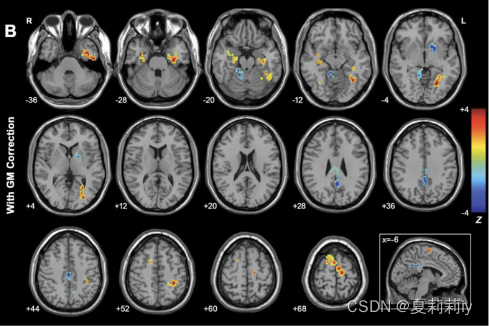

(4)Two-Sample T-Test

①One Sample是没有实际意义的,一般要使用Two-Sample来进行数据分析

②在左方添加两个文件夹(值第一组减去第二组的值,所以顺序很有关系)

③上图中Covariate Images添加的灰质密度图像,Covariate Images为图像协变量

④功能上一般是3*3*3的voxel size,但结构上一般是1*1*1或1.5*1.5*1.5。此时用Utilities→Image Reslicer可以将结构像变成功能像的大小,否则在这不一样大会报错

⑤上图中Text Covariates添加了头动,Text Covariates是文本协变量